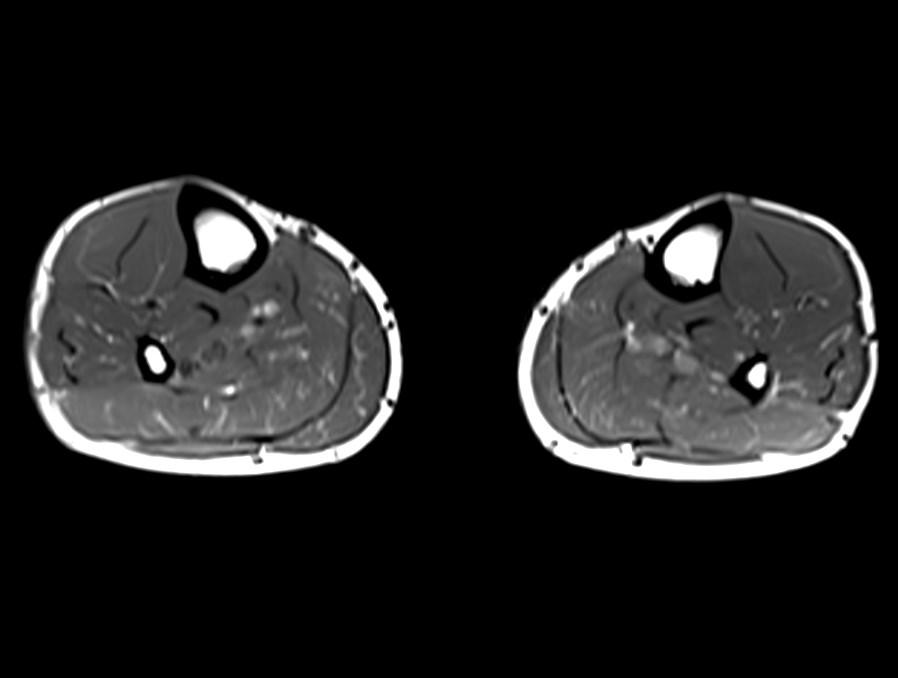

*29-year-old male present with pain in the right lower extremity for 3 days.

What is the most likely diagnosis?

Answer: Crural deep vein thrombosis

MR images showed perivascular edema, perifascial edema and the deep crural venous filling defects.